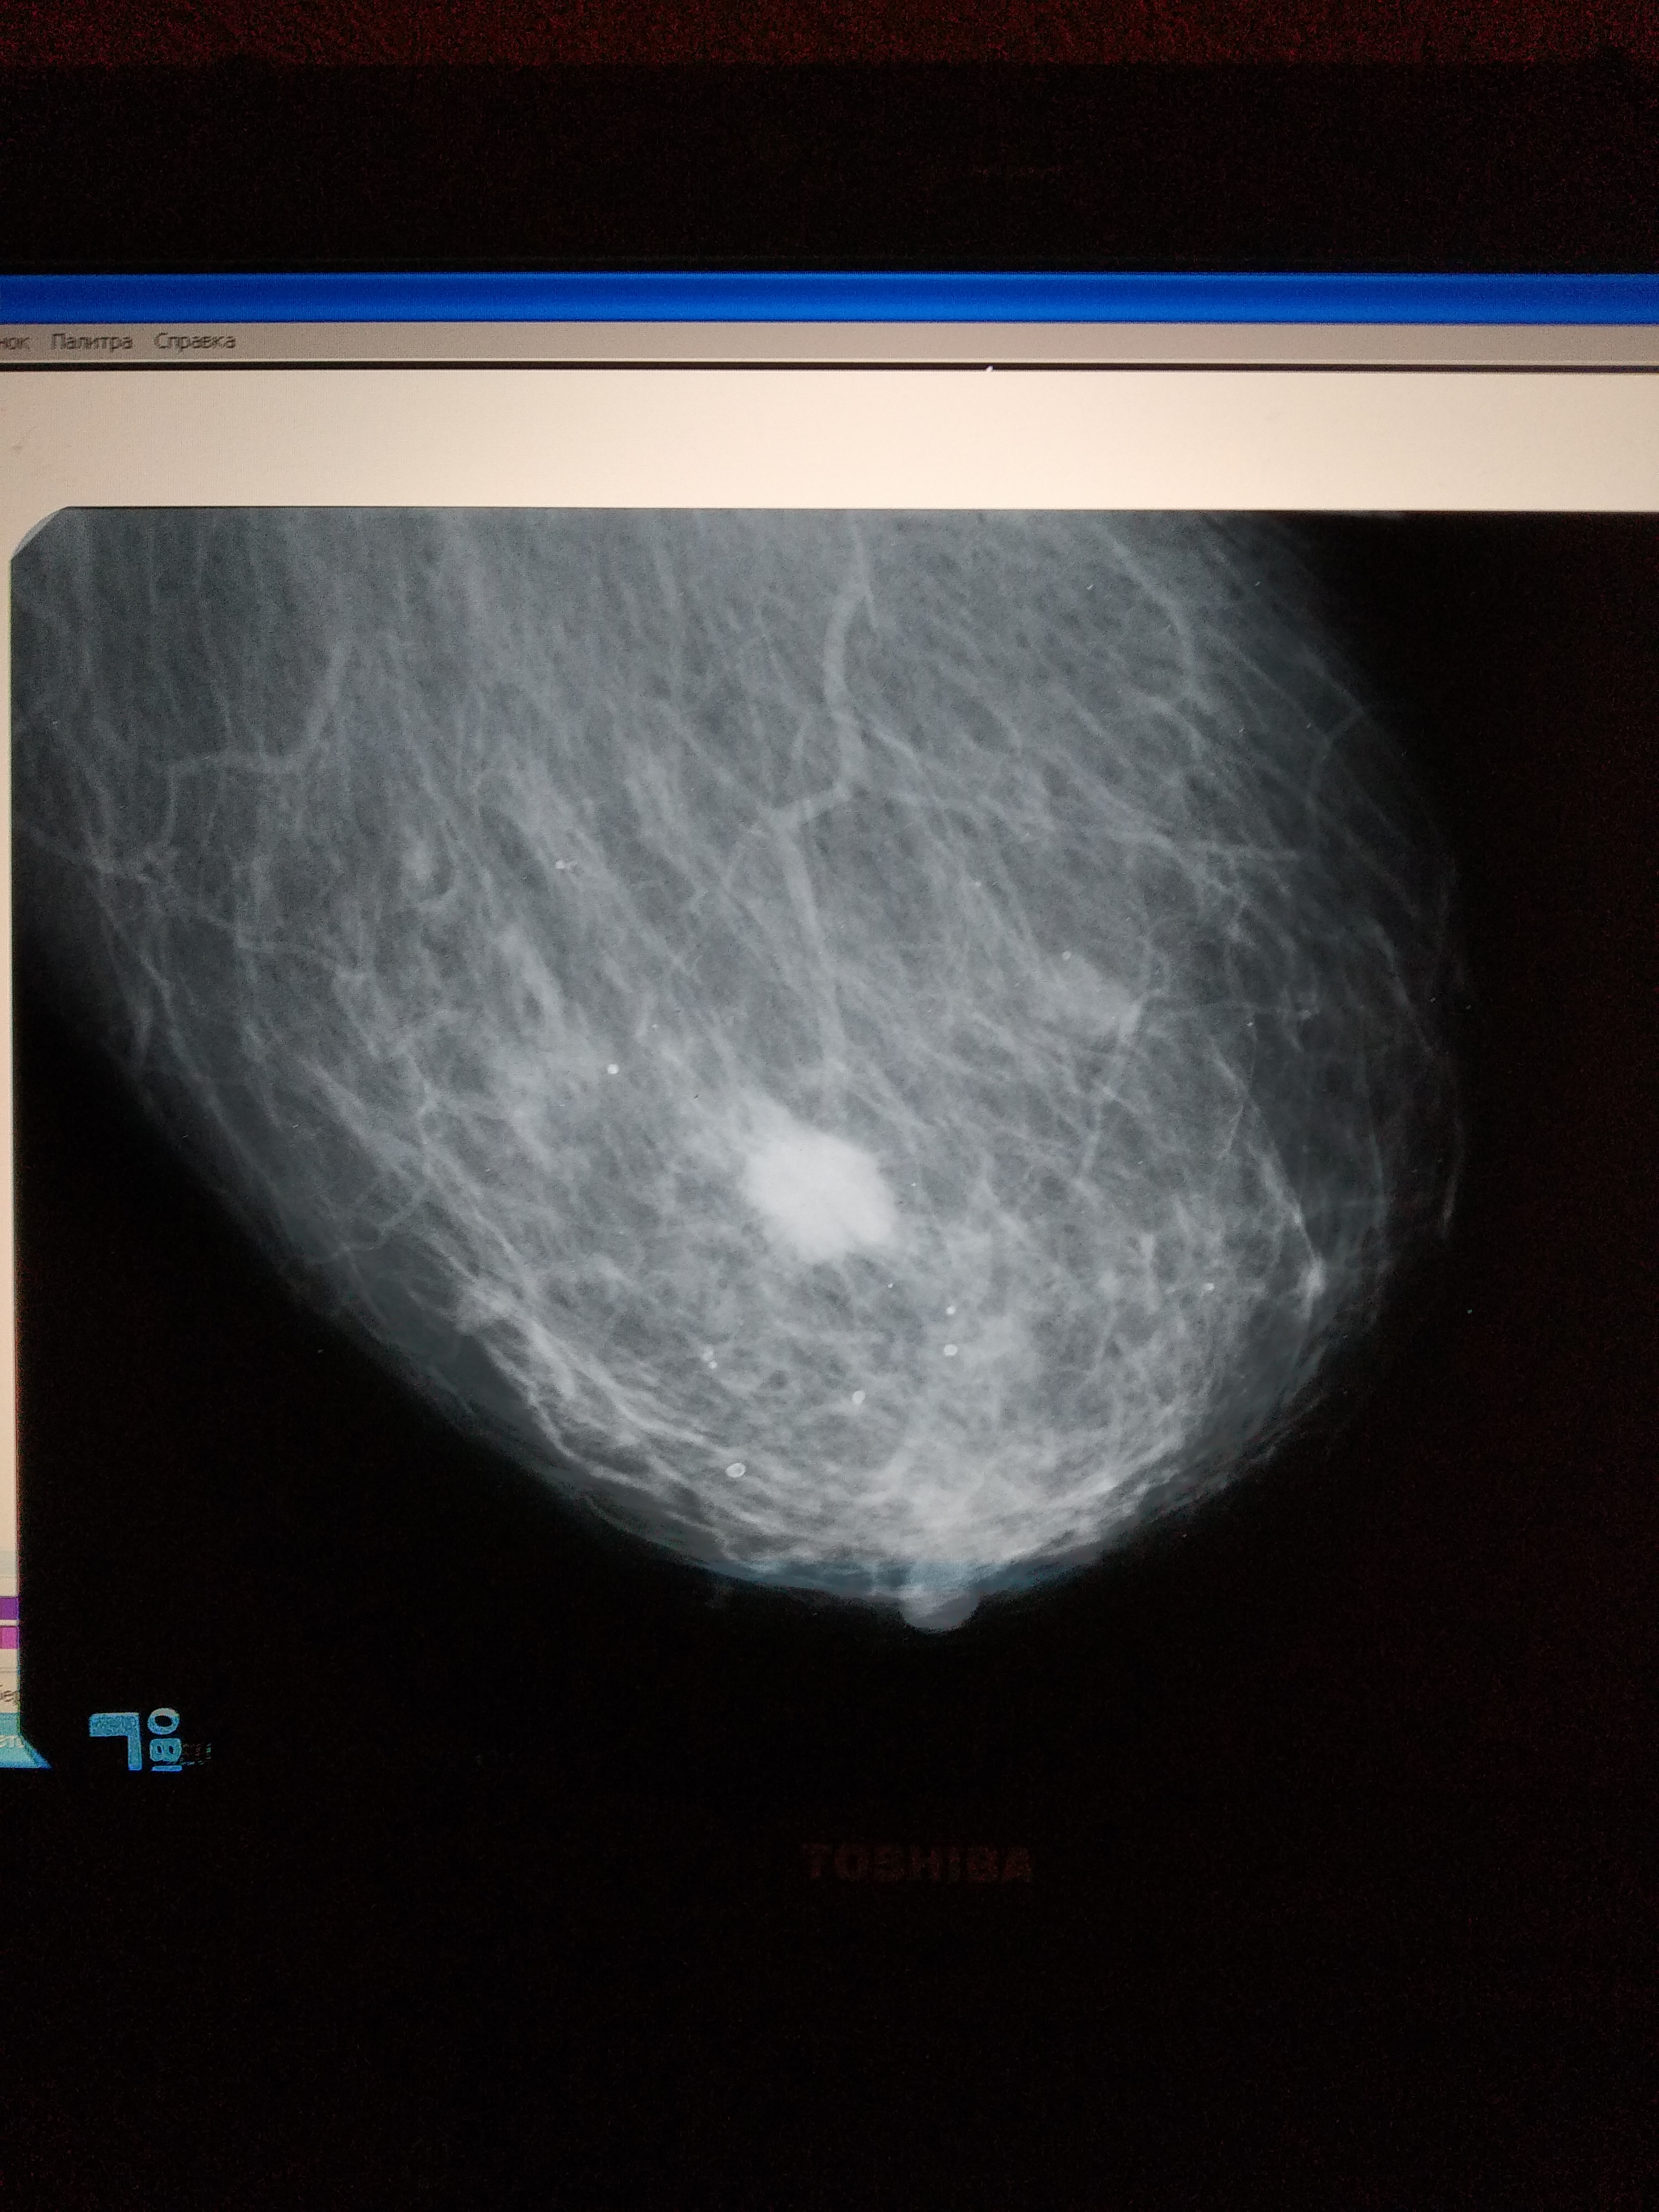

Фиброаденома молочной железы - доброкачественное образование, которое часто встречается у женщин. Оно может быть обнаружено при помощи различных методов диагностики, включая маммографию. Ниже представлены фотографии, помогающие понять, как выглядит данное заболевание.

Маммография и ее роль в диагностике фиброаденомы молочной железы

Маммография - это рентгенологическое исследование молочных желез. Оно позволяет выявить различные изменения в тканях, включая фиброаденому. На маммограммах можно увидеть структурные особенности опухоли и отследить ее динамику во времени.